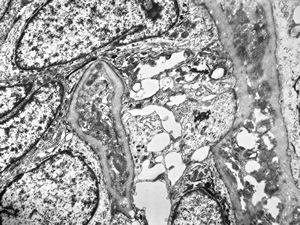

normal seromucinous salivary gland